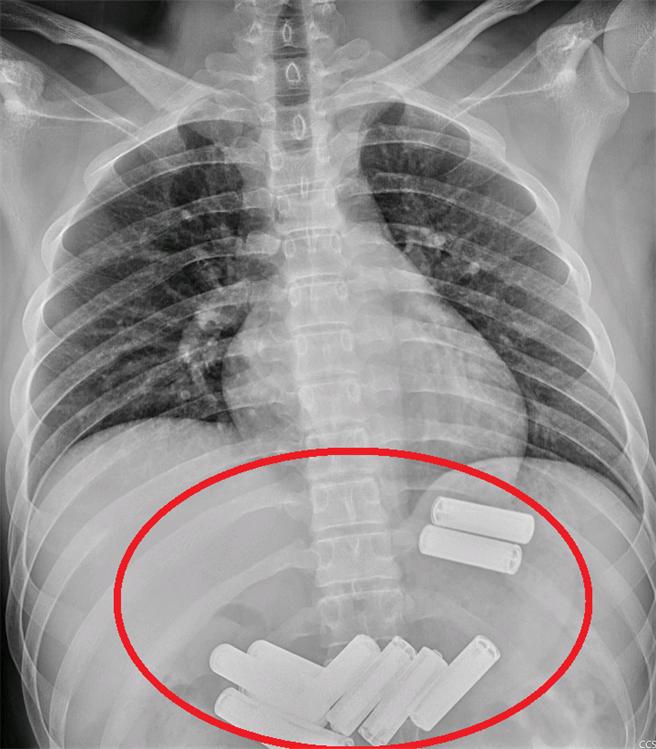

苗栗23岁李姓男子不明原因吞下11颗3号电池,半夜被紧急送至医院急诊,经腹部X光确认所有的电池都在胃中,透过胃镜检查发现,胃中还混合着不少食物,因此医师耗费约1小时,小心地一一取出,才顺利结束这场电池闹剧,也让李男吓得直喊不敢。

医师耗费1小时的时间,终于顺利将11颗电池取出。(大千医院提供/李京升苗栗传真)